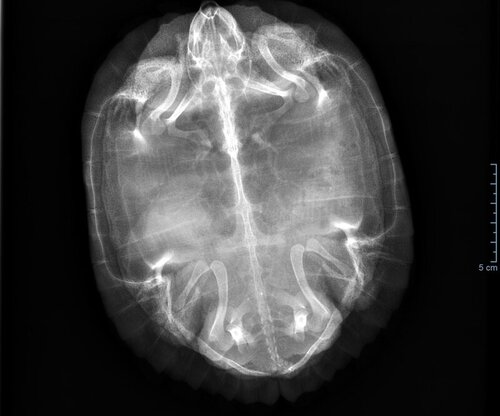

Даша17 Ваше имя: Дарья Локация: Россия, Зеленоград Опубликовано: 8 февраля 2023 Автор Опубликовано: 8 февраля 2023 @moth Зеленоград (Москва), 28 2. Красноухая 3. Акватеррариум 150 литров воды (именно воды) 41. Лампа накаливания есть над островом, работает где-то 12 часов 4.2. УФ лампа sylvania reptistar 10 (лампе 7 месяцев) 4.3. Берег встроенный 4.4. да, aquael ultramax 1000 4.5. Да, JBL, 25 градусов в воде грунт крупные камни 5. Температура 25 вода, на суше не знаю, но там лампа накаливания, тепло 6. С детства питание было рептомин, сначала бэби, потом джуниор, стикс, sera carnivor . Изредка (пару раз в месяц) были тигровые креветки, морковь, сверчки, гуппи живые. 7. Черепахе (девочке) 4 года, весит 980 г 8. С лета черепаха очень плохо ест. Последние полгода пытались кормить чем придётся- судак и щука сырые, тигровые креветки сырые, потом она и от них отказалась, на рептомин не реагирует вообще даже через голодовку 2 недели, серу может съесть 1 штуку в 2 дня, дальше уже выплёвывает. Подселили ей рыбок живых, она съела одну, вторую просто убила и не съела, с остальными уже 2 недели живёт в ладу. Никакое мясо никогда не давали. Летом ездили к врачу, врач заподозрила проблемы с яичниками и заметила компрессию лёгких, но подумали, что это из-за яичников. На прошлой неделе ездили в клинику, сделали повторный рентген (есть только эти свежие снимки, летних нет), и анализ крови (биохимия и общий). На рентгене замутнение в лёгких, я так поняла, как и летом. Испражняется черепаха на сходню острова, незаметно для нас, но стабильно сходня пачкается. Плавает без уклонов, дышит нормально, шею не раздувает, не кашляет. Один раз за эти полгода она чихнула и вылетело что-то на стекло, это было месяца 3 назад. По осмотрю внешнего вида врач дефектов не обнаружила. Сделали укол Элеовит 0.5 мл в попу. Прилагаю снимок и анализ крови, хотела бы узнать мнение, что может быть с черепахой